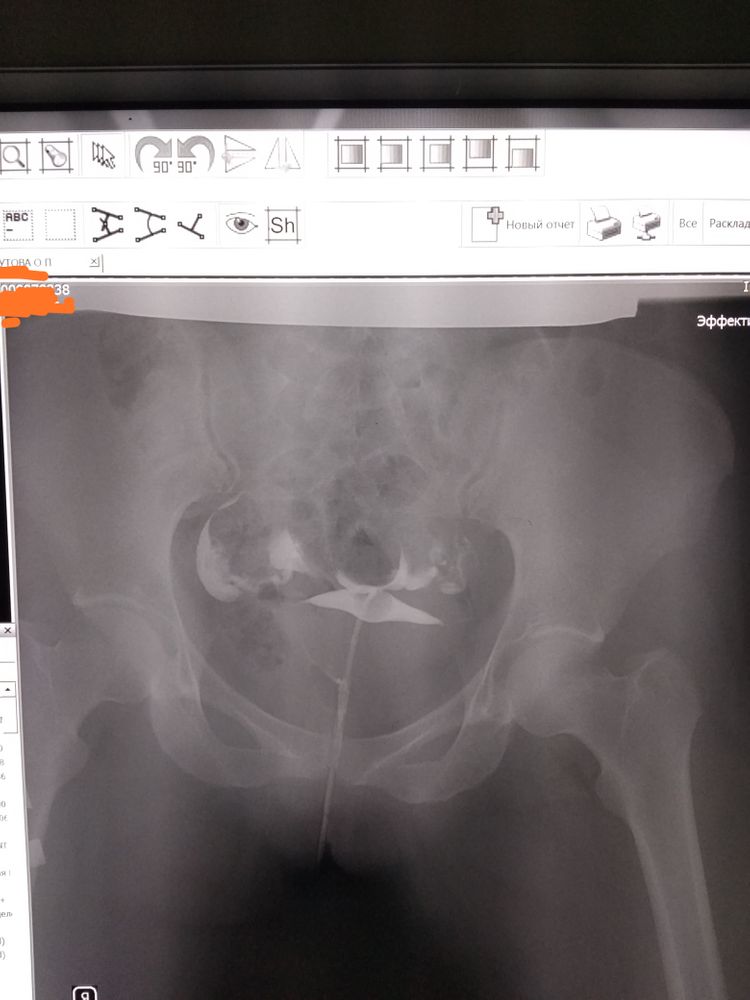

девочки, может кто-то разбирается... Должна была ехать на консультацию и записываться на лапару, но попала на самоизоляцию((( посмотрите, насколько здесь всё плохо на ваш взгляд) лично я вообще ничего здесь не понимаю))))

Kaba4ok, зачем? Это глупо, извините. Я могу написать что справа немного не проходимость, по количеству жидкости, а вот могу ошибаться. Зачем вам эти переживания

Солнце, мне врач выдал снимок и описание со словами "ну вы же понимаете, каждый врач этот снимок может интерпритировать по-своему..." Я не переживаю абсолютно, потому что в любом случае пойду на лапару. Просто интересно. И скучно на самоизоляции)